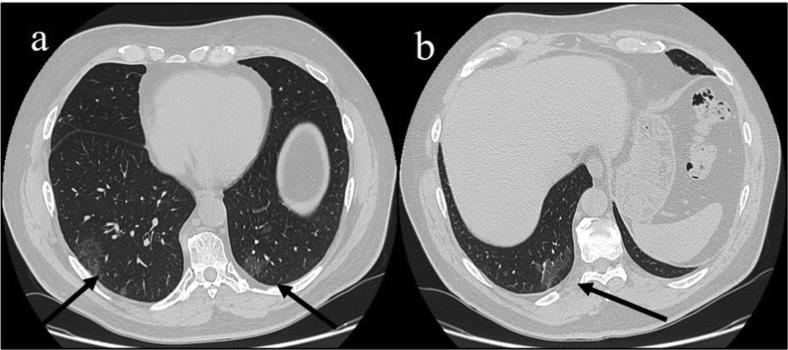

Typical CT findings of COVID-19 pneumonia in patients presenting with repetitive negative RT-PCR.

Multiple polymerase chain reaction (RT-PCR) is considered the gold standard diagnostic investigation for severe acute respiratory syndrome coronavirus 2 (SARS-CoV-2) that causes coronavirus disease 2019 (COVID-19). However, false negative multiple polymerase chain reaction (RT-PCR) results can be diagnostically challenging. We report three patients with history of fever and different clinical signs. During the height of the pandemic in Italy (March to May 2020), these patients underwent chest computed tomography (CT) scans that showed lung alterations typical of COVID-19 with multiple negative RT-PCR tests and positive serology for SARS-CoV-2. Two of the three patients showed residual pneumonia on CT after the onset of the first clinical signs. One patient presented with diarrhoea without respiratory symptoms. These cases suggest that in the COVID-19 pandemic period, to provide an earlier specific treatment in patients with positive serology, a chest CT scan can be useful in those presenting with a fever or a history of fever associated with persistent mild respiratory symptoms or with abdominal complaints despite repeated negative RT-PCR results.